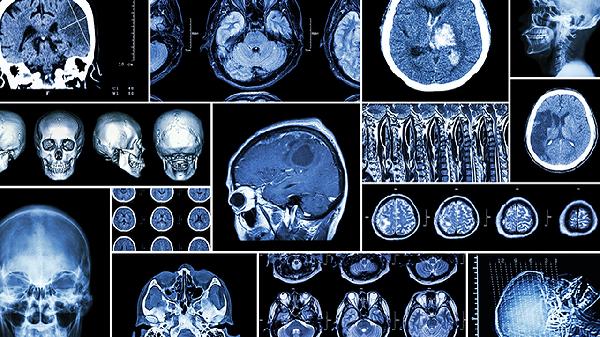

脑血栓患者需长期控制血压、血糖和血脂,戒烟限酒,保持低盐低脂饮食。每日进行适度有氧运动如散步或太极拳,避免久坐不动。定期复查颈部血管超声和头颅CT,监测病情变化。出现头晕、肢体无力等复发征兆时立即就医。保持患者情绪稳定,家属需学习基本护理技能。